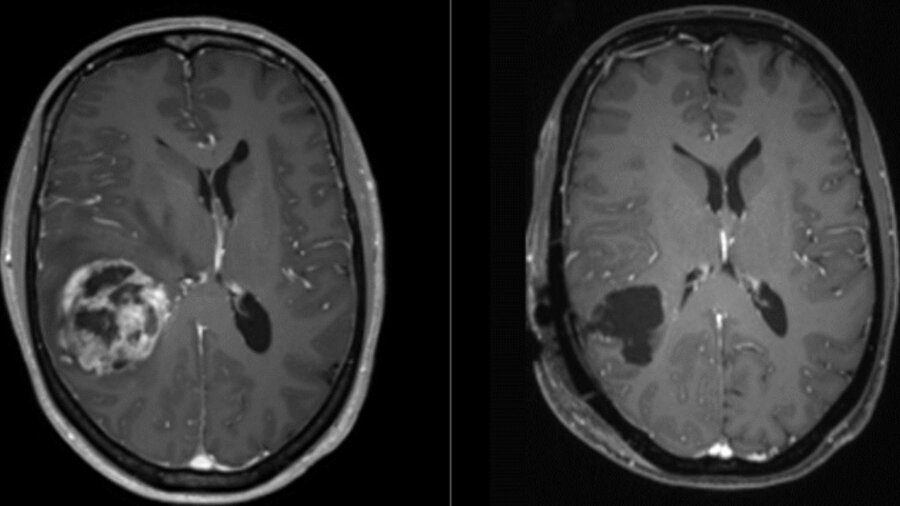

Tıp dünyasını sarsan gelişme: Burun damlasıyla beyin tümörlerini yok etmek mümkün!

Araştırmacılar, burun yoluyla uygulanan damlaların merkezi sinir sistemine ulaşarak ölümcül beyin kanseri glioblastomaya karşı etkili olabileceğini gösterdi. Farelerde yapılan deneyler, ilacın hedefe güvenli şekilde ulaştığını ve tümör büyümesini önlediğini ortaya koydu. Bu yöntem, geleneksel tedavilere dirençli tümörler için yeni bir umut vadediyor.

Deneylerde, bu nano taşıyıcılar STING yolunu etkin bir şekilde aktive ederek tümör büyümesini engelledi. Araştırmacılar, nazal damla ile diğer bağışıklık güçlendirici ilaçların kombinasyonunun farelerde uzun vadeli bağışıklık sağladığını belirtti. Bu, glioblastomaya karşı yeni bir stratejinin ilk somut adımı olarak değerlendiriliyor.

Hayatta kalma oranı %6,9

Araştırmacılar, insan klinik denemelerine ulaşmanın henüz zaman alacağını ve yöntemin diğer tedavilerle desteklenmesi gerektiğini vurguluyor. Glioblastoma, beyin kanserleri arasında en yaygın ve ölümcül tür olarak biliniyor; teşhis sonrası beş yıl hayatta kalma oranı yalnızca %6,9.